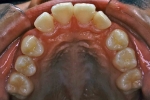

初診時